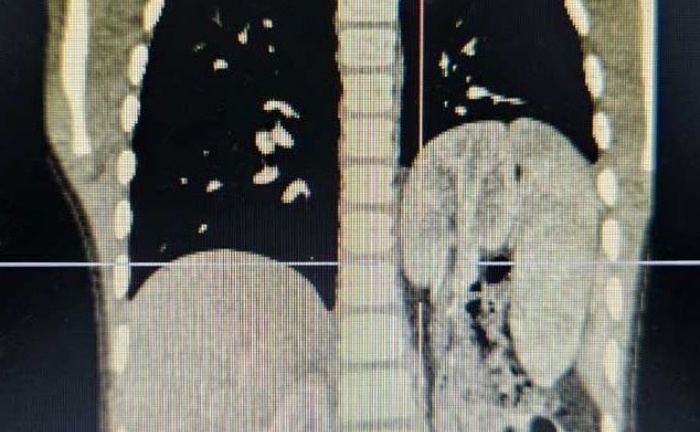

Các bác sĩ Bệnh viện Thuận Mỹ ITO Đồng Nai vừa tiến hành phẫu thuật thành công cho nam bệnh nhân 72 tuổi có khối sỏi bàng quang to như quả trứng ngỗng.